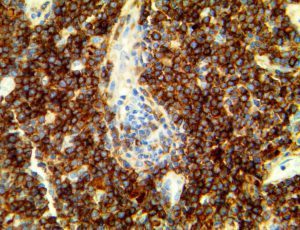

The first cytokines released are interleukin 1β (IL-1β) and tumor necrosis factor-α (TNF-α), which attract a variety of circulating white blood cells (WBCs) to the infection site, including neutrophils, monocytes, macrophages, and natural killer (NK) cells. This response, along with the antipathogenic chemicals released by these cells (i.e., complement), comprise the innate immune response. These cells directly attack the invading pathogen and also release additional cytokines, chief among them interleukin-1 and 6 (IL-6). IL-6 is essential for invoking the adaptive immune response, which calls T-cells, B-cells, and T helper (Th) cells to the infection site. IL-6 also stimulates further recruitment, proliferation and activation of macrophages.

It is the ICU physician who is most likely to witness one of the deadliest manifestations of the abnormal immunological response, the cytokine storm syndrome (CSS). This response is also referred to by some as the cytokine release syndrome (CRS). CSS is characterized by continuous activation and expansion of macrophage and lymphocyte populations, which secrete large amounts of cytokines, causing the cytokine storm. This massive cytokine release is akin to hemophagocytic lymphohistiocytosis (HLH) disease, a syndrome characterized by initial unchecked and persistent activation of cytotoxic T lymphocytes and NK cells.

This activation induces inflammatory monocytes to highly express IL-6, starting a localized and then systemic cascade effect that results in hyperproduction of IL-6, which accelerates the inflammatory process. Because IL-6 also increases vascular permeability, excessive levels cause blood vessels to become very leaky. This, along with clotting factors released from vascular endothelial cells, stimulates the coagulation cascade, resulting in microthrombosis (tiny clots), which leads to ischemia and tissue death of the kidney, intestines, heart, liver, brain and extremities.